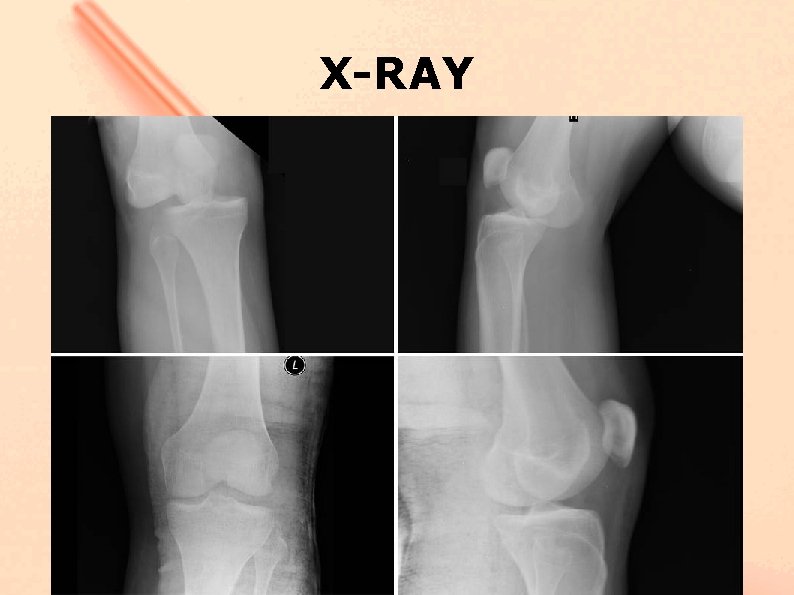

Case I - 19 year male, left knee injured by falling from stairs. Full knee dislocation has occurred. The dislocated limb was reposed and immobilized with brace. No surgery was applied. - MRI – ACL, LCL, PLC injury was diagnosed - neurology – complete CPN palsy.

Case I - Surgery was performed 5 months after injury - No signs of nerve repair was noted - Huge knee varus instability >15 degrees - External rotation 55 degrees - Pivot shift +++ - Lachman ++ - Anterior drawer ++

X-RAY

• Mrt / ro